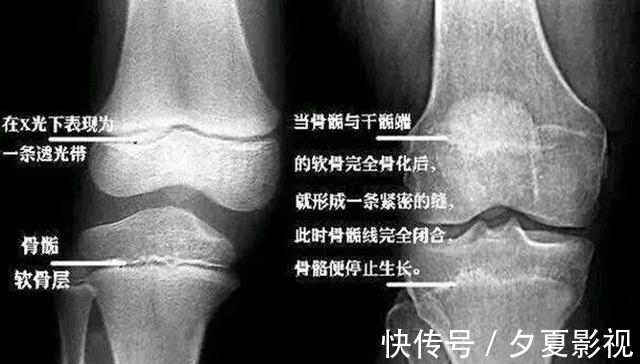

殊不知,孩子性早熟并不只是“成长提前了”这么简单,还会带来一系列危害。比如提前发育的外观,会让孩子觉得自己跟同龄人不一样,从而有自卑、羞耻感等心理。另外,性早熟还会让骨龄提前,引起骨骺线提前闭合,导致孩子达不到遗传身高。